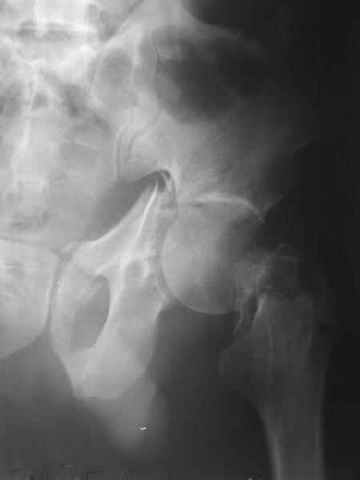

Контрольный снимок перед разрешением нагрузки прямой 13/10/03

|

Больной 18 мая 2003 года в автоаварии получил перелом левой вертлужной впадины, вывих бедра. Госпитализирован в один из стационаров области.Вывих вправлен. В последствии бедро вывихивалось еще дважды. На консультацию был представлен снимок от 19.05.03г., больной переведен к нам 3.06.03г. Снимок при поступлении - перелом впадины, задне-верхний вывих бедра. 05.06.2003 г. выполнено открытое вправление вывиха левого бедра и остеосинтез стенки вертлужной впадины двумя винтами. Послеоперационный период без осложнений. Объем движений в левом тазобедренном суставе восстановился полностью. Выписан на амбулаторное лечение в удовлетворительном состоянии с рекомендациями 3 месяца ходить на костылях без нагрузки на оперированную конечность. На контрольных рентгенограммах левого тазобедренного сустава 13.10.2003 г. - признаки консолидации перелома; плотность, форма головки и состояние суставных поверхностей удовлетворительные. Разрешена дозированная осевая нагрузка, на конечность с использованием дополнительной опоры. 19.12.2003 г. больной обратился с жалобами на боли в левом тазобедренном суставе. На рентгенограммах левого тазобедренного сустава 19.12.2003 г., 20.02.04г. - асептичекий некроз головки бедра. 5.04.04г. - эндопротез. Сейчас ходит без трости, не хромает. Особенность эндопротезирования - при удалении винтов прослежена линия перелома заднего края впадины и предложено установить чашку несколько меньшего диаметра, чтобы она была покрыта несломанной частью.